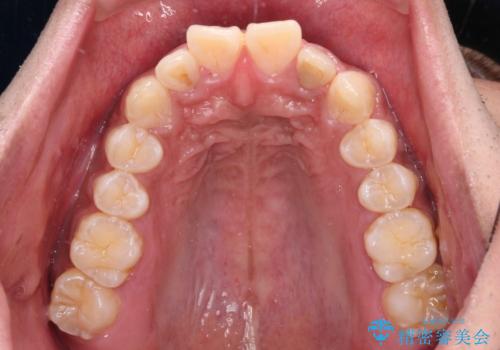

- 深く咬みこみ、前に飛び出した上顎前歯を気にして来院された患者様です。

口元の突出感はあまりありませんでしたが、上顎歯列が全体的に前方にあり、更には下顎歯列が深く咬みこんでいるために、上顎前歯が前方に突出している状態でした。

抜歯は行わず、補助装置を用いて上顎歯列全体を後方移動させ、ワイヤー装置にて奥歯の咬み合わせを改善していくこととしました。